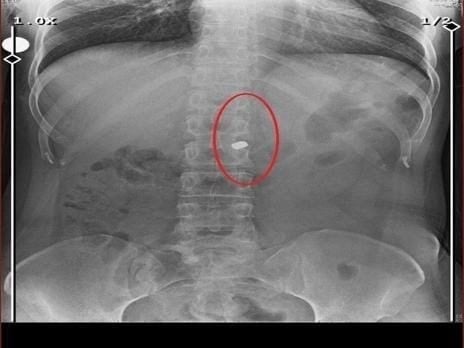

Cinayetin ardından aynı silahla sevgilisini hedef alan Sarıkaya, Fatma O.’yu 8 kurşunla yaraladı. Özaslan’ın cesedini önce çarşafa, ardından kokuyu önlemek için streç filme sararak sakladı. Sarıkaya, yaralı sevgilisinin hastaneye gitmesine izin vermedi; eczaneden aldığı malzemelerle pansuman yaptı. İddianameye göre Sarıkaya, yaralı halde rehin tuttuğu kadına 21 gün boyunca cinsel saldırıda bulundu.